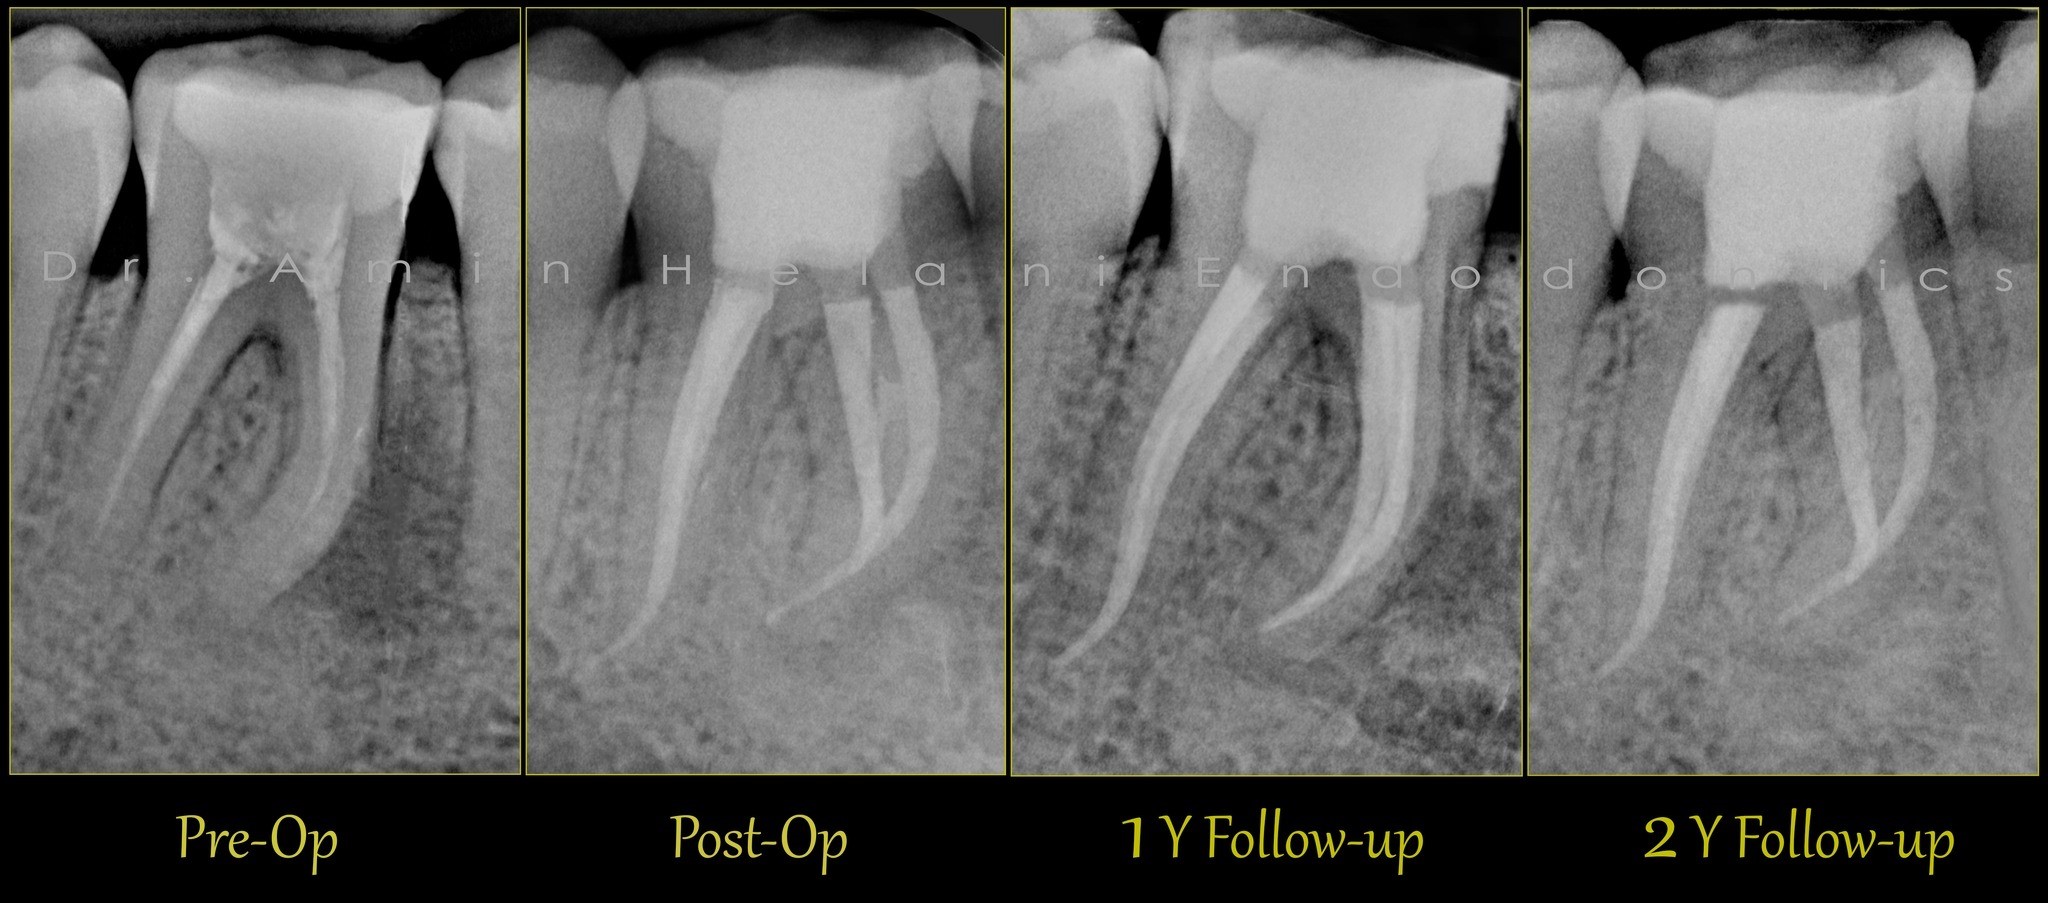

tiefe Aufteilung + Heilung